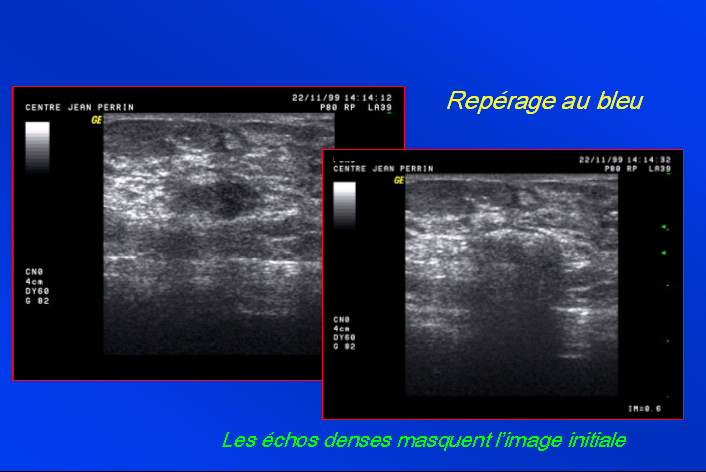

Repérage au bleu sous échographie.

Abord direct. Vérification du « tip écho », marquage

cutané au point de ponction.